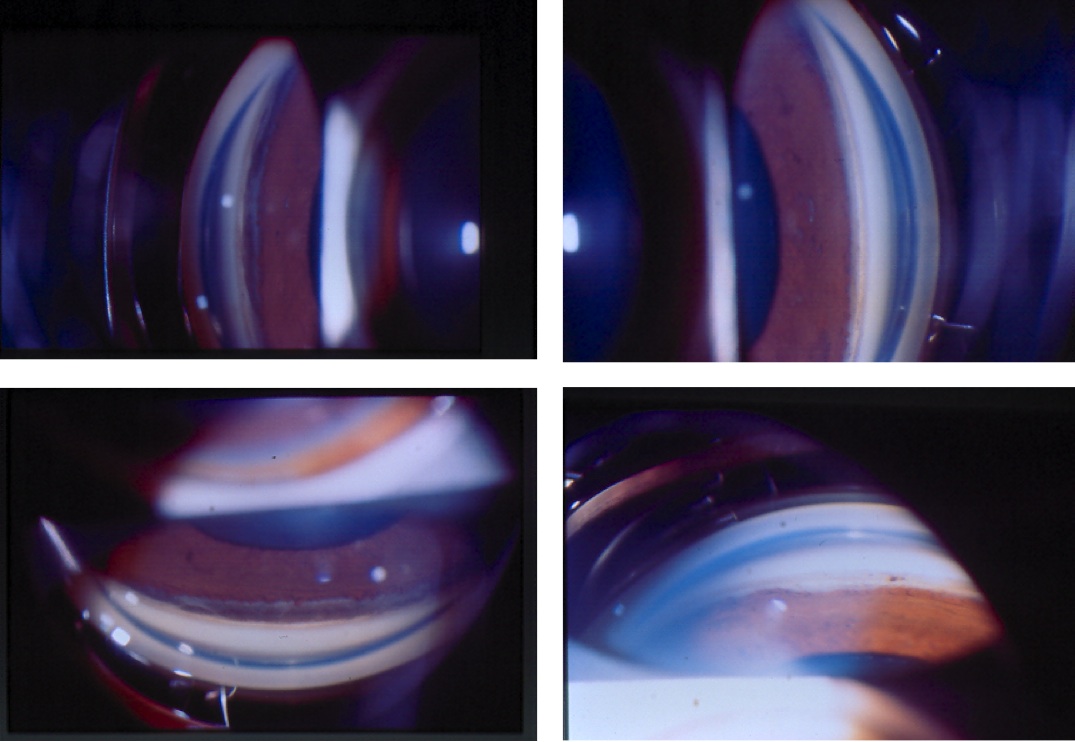

Figure 2. UBM demonstrating cyclodialysis cleft in patient (a) above

On gonioscopy, a cyclodialysis cleft is visible as an abnormal region posterior to the scleral spur displacing the iris root and ciliary body posteriorly. The appearance of the cleft region can vary considerably, and can look white (like sclera), black, or gray (Figure 1(a) & (b)). Clinical evaluation by gonioscopy is often difficult in a soft eye with a shallow or flat anterior chamber, and can be further impaired by corneal folds/edema or hyphema after trauma. Injection of viscoelastic into the anterior chamber, with or without application of topical pilocarpine to maximally open the angle, can improve the view. Sometimes, a cleft may be hidden adjacent to broad-based peripheral anterior synechia; such areas should be carefully inspected during gonioscopy. In many cases, complementary use of imaging (see section 2.3 Imaging, below) is necessary to confirm the diagnosis and gauge the size of the cleft.[1]